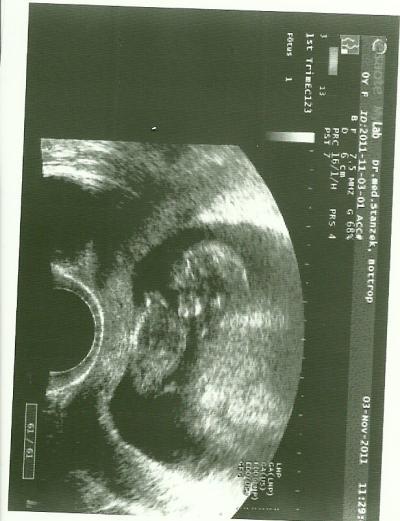

Da ich halb krank vor Sorge um meinen Krümel war, machte ich mich heute auf den Weg zu dem Vertretungsarzt meines FAs. Und.. was soll ich sagen.. KRÜMEL GEHT ES RICHTIG GUT :)

Bild zu Die überglücklichste Mami meldet sich :) - Forum für Mai - Mamis